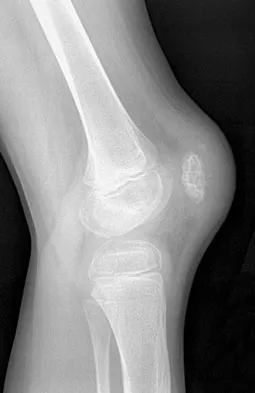

A 19-year-old man has had pain and swelling in his left forearm for the past 8 months. Laboratory studies show a mildly elevated WBC count and erythrocyte sedimentation rate. Radiographs are shown in Figures 58a and 58b, a CT scan is shown in Figure 58c, and T1- and T2-weighted MRI scans are shown in Figures 58d and 58e, respectively. A biopsy specimen is shown in Figure 58f. Immunohistochemistry demonstrates that the lesion is negative for leukocyte common antigen (CD34). What is the most common cytogenetic translocation associated with this lesion?

Explanation

The imaging studies show a permeative lytic destructive lesion in the proximal radius with "hair-on-end" periosteal reaction and a large soft-tissue mass most consistent with Ewing's sarcoma. The pathology reveals monotonous sheets of "round blue" cells. This limits the differential diagnosis to primary lymphoma of bone versus Ewing's sarcoma. These are best differentiated by immunohistochemistry, cytogenetics, and flow cytometry. Lymphoma of bone is typically CD34 positive and CD99 negative; whereas, the reverse is true of Ewing's sarcoma, CD34 negative and CD99 positive. The most common cytogenetic translocation with Ewing's sarcoma is 11; 22; 21; 22 and 7; 22 translocations have also been reported in Ewing's sarcomas. The X; 18 translocation is most commonly associated with synovial cell sarcomas; the 12; 22 translocation is most commonly associated with clear cell sarcomas; the 2; 13 translocation is most commonly associated with alveolar rhabdomyosarcomas, and the 12; 16 translocation is most commonly associated with myxoid liposarcomas. Flow cytometry is used to characterize the cell types of lymphomas. Womer R: The cellular biology of bone tumors. Clin Orthop Relat Res 1991;262:12-21. Yamaguchi U, Hasegawa T, Morimoto Y, et al: A practical approach to the clinical diagnosis of Ewing's sarcoma/primitive neuroectodermal tumour and other small round cell tumours sharing EWS rearrangement using new fluorescence in situ hybridisation probes for EWSR1 on formalin fixed, paraffin wax embedded tissue. J Clin Pathol 2005;58:1051-1056.